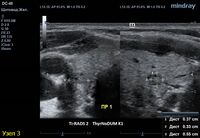

3) Узел правой доли, не прорастает капсулу щитовидной железы (0 баллов), больше широкий чем высокий (0 баллов), не имеет кальцинатов (0 баллов), с ровным четким контуром (0 баллов), изоэхогенный (1 балл), смешанной структуры (1 балл). Количество баллов 2, ACRTi-RADS2, ThyrNoDUMК1. Пункция не показана в связи с низким риском.

4) Узел правой доли, не прорастает капсулу щитовидной железы (0 баллов), больше широкий чем высокий (0 баллов), не имеет кальцинатов (0 баллов), с ровным четким контуром (0 баллов), изоэхогенный (1 балл), смешанной структуры (кистозно солидный) (1 балл). Количество баллов 2, ACRTi-RADS2, ThyrNoDUMК1. Пункция не показана в связи с низким риском.